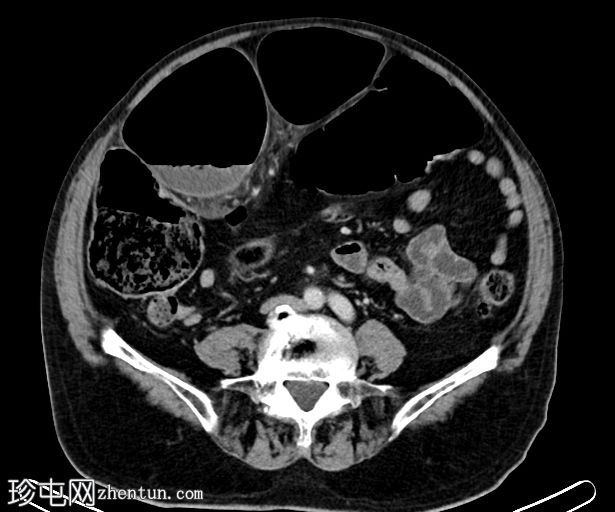

轴位增强扫描(门静脉期)

乙状结肠系膜呈漩涡征,乙状结肠袢扩张且冗长。乙状结肠和直肠下游塌陷。结肠上游扩张。小肠袢未见扩张。乙状结肠系膜少量积液,脂肪条索状改变。腹膜内未见游离气体。